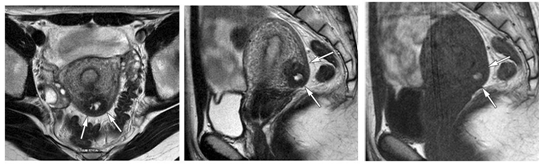

CHT cũng là kỹ thuật không xâm lấn có thể chẩn đoán lạc tuyến trong cơ tử cung (LTTCTC) với độ nhạy (78-88%) và độ đặc hiệu (67-93%) cao. Kỹ thuật này tốt hơn SA ngả âm đạo không những trong mô tả vị trí và độ lan rộng của tổn thương mà còn có ích trong phân biệt LTTCTC với u xơ tử cung (UXTC) trong những trường hợp khó. Trên CHT, LTTCTC có biểu hiện dày lan tỏa hay khu trú hoặc từng đoạn của vùng chuyển tiếp hay vùng nối (junctionalzone) của cơ tử cung, tạo thành vùng tín hiệu thấp giới hạn không rõ, thỉnh thoảng bên trong có các ổ nhỏ tín hiệu cao trên T2W. Tiêu chuẩn chẩn đoán trên CHT khi vùng nối dày khu trú hay lan tỏa >12mm, thường ở thành sau, không ở CTC, hiếm khi không tiếp xúc với vùng nối, mất ranh giới với nội mạc, hình dạng vô định, không tạo hiệu ứng khối u và ít khi gây biến đổi đường bờ nội mạc. Về mô học, vùng tín hiệu thấp tương ứng các cơ trơn bị phì đại và cá cổ tín hiệu cao trên T2W tương ứng với nội mạc lạc chỗ và giãn thành các nang. Khi hành kinh, các nội mạc lạc chỗ này xuất huyết thì sẽ có tín hiệu cao trên T1W và T1W xóa mỡ.

Hình10.Lạc tuyến trong cơ tử cung ở thành trước tử cung

SagittalT1W: tử cung kích thước lớn, tín hiệu đồng nhất.

SagittalT2W: tổn thương tín hiệu thấp, giới hạn không rõ ở thành trước tử cung với vô số ổ nhỏ tín hiệu cao bên trong

Hình11. LTTCTC ở thành trước tử cungvới các ổ xuất huyết bên trong